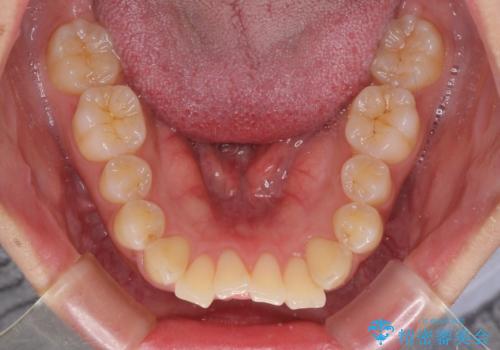

- 前歯の突出感を気にして来院された患者様です。

咬合力が非常に強く、咬合力で前歯が前方に押し広げられており、上下唇に閉じにくさが認められました。

上下左右の第一小臼歯4本を抜歯し、ワイヤー装置にて矯正治療を行うこととしました。